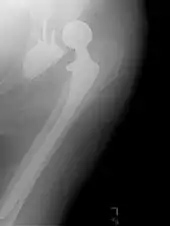

Hemiarthroplasty

Hemiarthroplasty is a surgical procedure that replaces one half of the joint with an artificial surface and leaves the other part unchanged. This class of procedure is most commonly performed on the hip after an intracapsular fracture of the femur neck (hip fracture). The procedure is performed by removing the head of the femur and replacing it with a metal or composite prosthesis. The most commonly used prosthesis designs are the Austin Moore and Thompson prostheses. A composite of metal and HDPE that forms two interphases (bipolar prosthesis) can be used. The monopolar prosthesis has not been shown to offer any advantage over bipolar designs. The procedure is recommended only for elderly/frail patients, due to their lower life expectancy and activity level. This is because over time the prosthesis tends to loosen or to erode the acetabulum.[86] Independently mobile older adults with hip fractures may benefit from a total hip replacement instead of hemiarthroplasty.[87]

Hip prosthesis for hemiarthroplasty. This example is bipolar, meaning that the head has two separate articulations.

X-ray of the hips, with a right-sided hemiarthroplasty